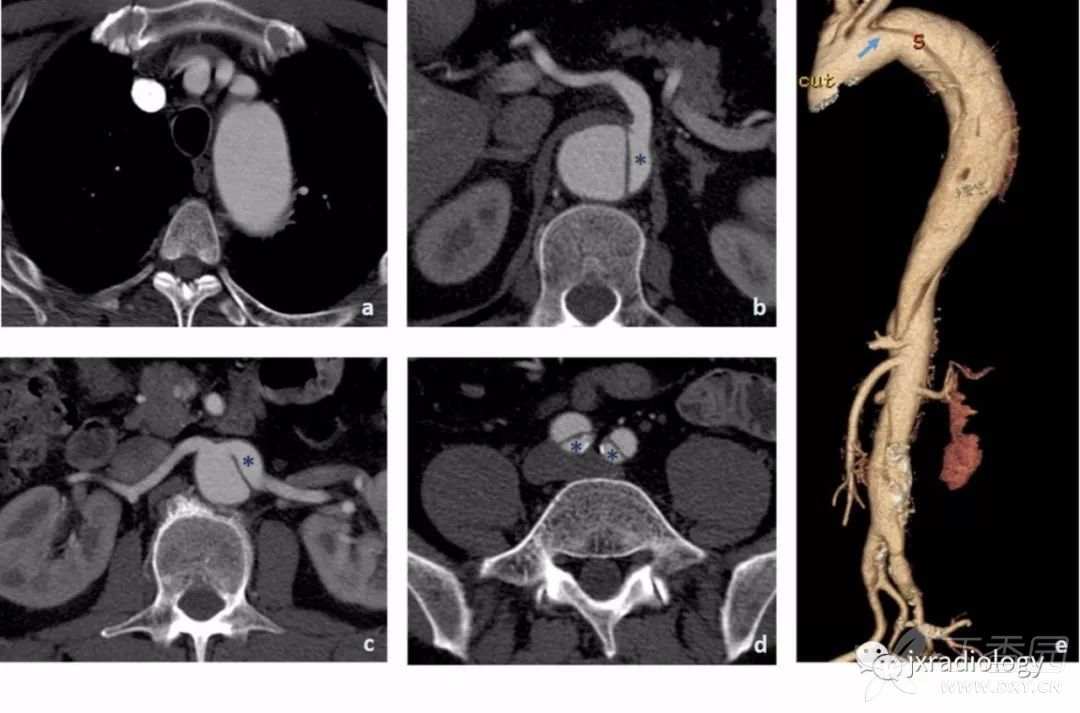

主动脉夹层扩展至主动脉弓上分支不常见(约5-10%),但应提示,因为它可导致脑缺血( 图17 )。

图17:CT示升主动脉中的内膜瓣(a和b图箭头)延伸至降主动脉。内膜瓣延伸到头臂动脉,可见血栓形成(c图箭头显示头臂动脉中的血栓,d图显示颈动脉血栓形成的征象 - 星号显示左颈动脉中,而右颈动脉未见显示)。

- 对夹层延伸至髂血管也可能提示下肢缺血的风险( 图18 )。

图18:增强后CT显示主动脉夹层Stanford B型(内膜瓣不延伸到左锁骨下动脉的开口处 a和e)。

腹腔干、肠系膜上动脉从真腔中开口(b图星号),以及左肾动脉(c图星号),右肾动脉从假腔开口。 夹层延伸超过主动脉分叉累及髂总动脉。